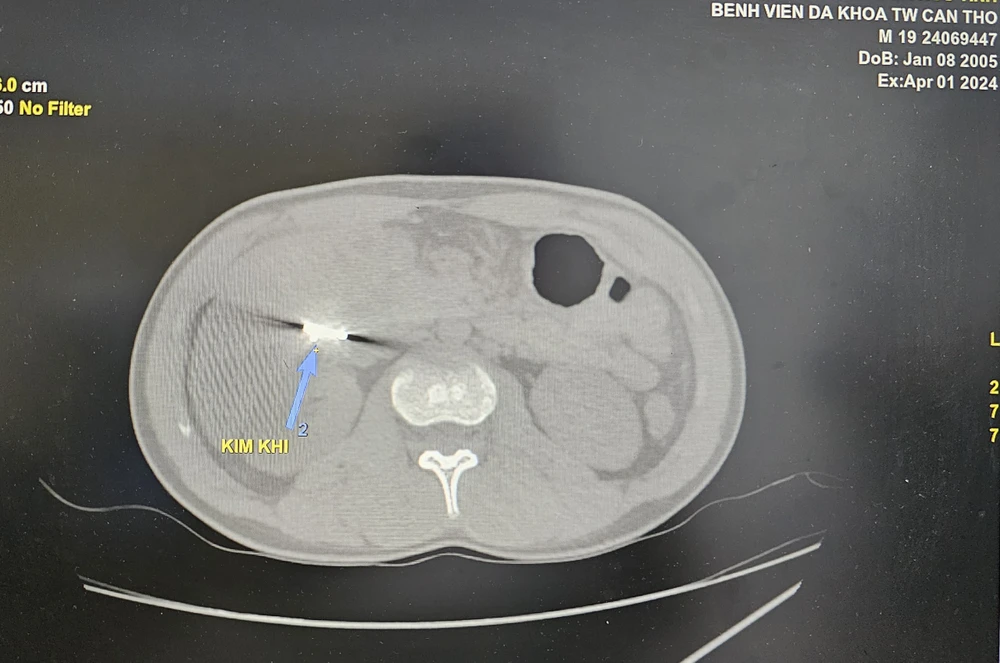

Hình ảnh dị vật là mắt xích máy cưa nằm trong ổ bụng bệnh nhân. Ảnh: BVCC

Kết quả chụp cắt lớp vi tính bụng có cản quang ghi nhận dị vật cản quang kim loại dưới gan phải kích thước #2x1cm, áp xe vùng hạ sườn phải kích thước #5x3cm. Bệnh nhân có chỉ định phẫu thuật nội soi lấy dị vật.